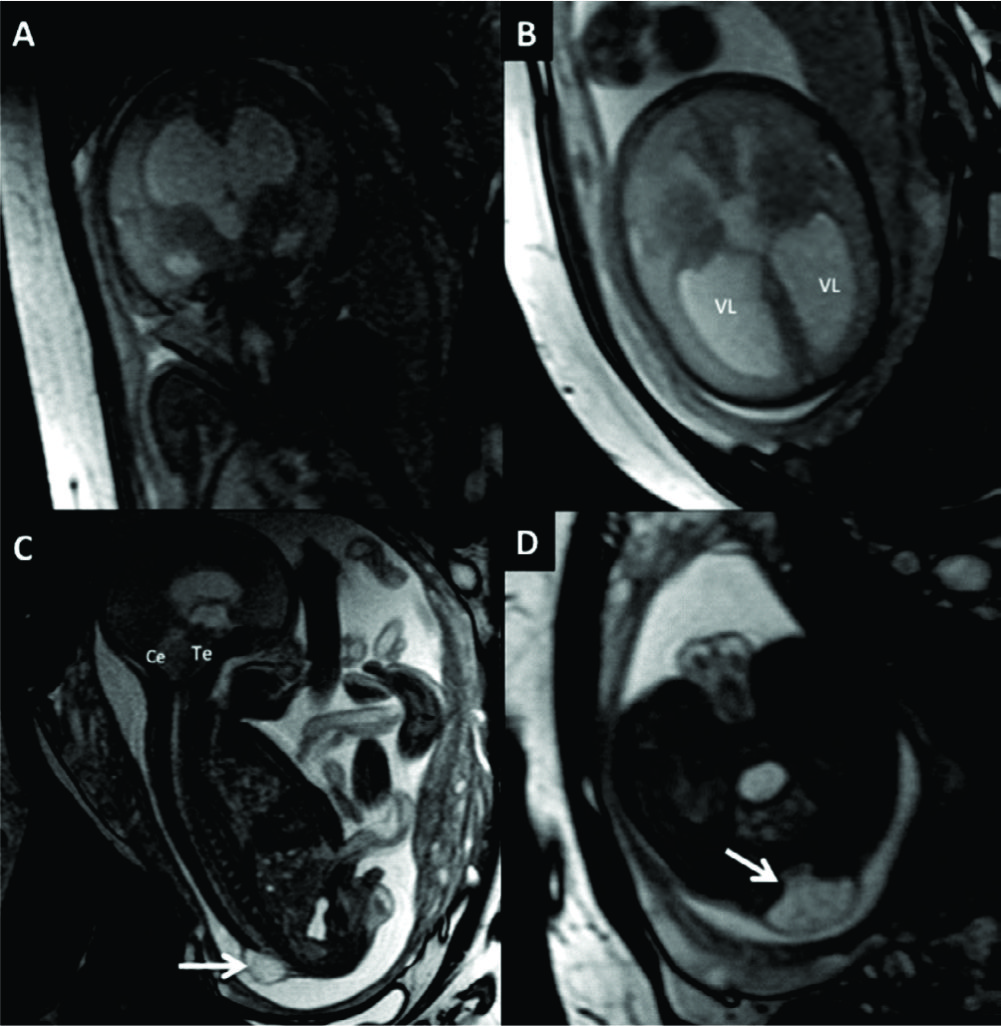

Figura 10

RM Fetal en Malformación de Chiari.

Estudio realizado a las 29 semanas con diagnóstico ecográfico de mielomeningocele. En imagen coronal (A) se observa la severa dilatación del sistema ventricular supra-tentorial lo que se corrobora en la imagen axial (B) con una disposición colpocefálica de los ventrículos laterales (VL). En la imagen fetal sagital (C) se reconocen el cerebelo (Ce) y tronco encefálico (Te) sin identificarse claramente el IV ventrículo lo que indica una disminución de las dimensiones de la fosa posterior. En el mismo plano se observa el defecto de cierre posterior del tubo neural (è) con un saco de meningocele. La imagen axial a nivel de ese saco (D) muestra claramente el defecto espinal posterior (è) aunque sin observarse claramente el contenido neural del mismo.